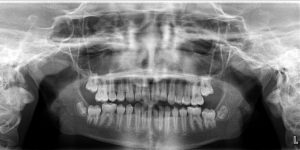

An 11.3 year old caucasian female presents with a chief concern that “my teeth don’t come together.”